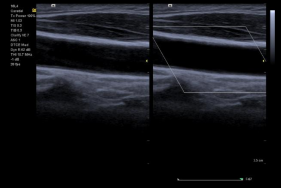

Clarify vascular enhancement(VE) 血管增强 : 西门子的专利技术:不影响空间分辨率的同时提高组织对比分辨率,使得管腔内的结构显示更加清晰,临床价值:对于管壁内中膜、斑块和血栓的判定更加准确。应用范围广。